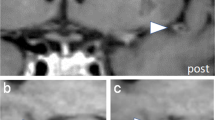

Among 8772 screened intracranial arteries, 590 arteries exhibited significant stenosis (86 ICAs, 153 MCAs, 40 ACAs, 61 PCAs, 23 BAs, and 69 VAs). The in-house vessel analysis software extracted arterial features relatively well, and representative cases are demonstrated in Fig. 2. For each vessel, the ICA, basal and distal MCA had missing curvature values ranging from 0.2 to 3.9%. The basal and distal ACA had missing values ranging from 2.5 to 10.9%. In the posterior circulation, 18.4% of the left VA and 34.7% of the right VA were missing due to hypoplasia and dominance, and 18.4% of the BA was missing. For the PCA, missing values ranged from 2.3 to 2.5% for the basal PCA and from 37.6 to 39.3% for the distal PCA. The cerebellar artery was missing between 3.1 and 5.2%. The curvaturem of the intracranial arteries were mostly symmetric in the right and left intracranial arteries and the curvaturem of the BA was lowest. The intracranial arteries in the posterior circulation and the distal arteries tended to have relatively higher tortuosity (Supplementary Table 1).

Analysis of intracranial arteries using an in-house vessel analysis software. (A) Intracranial time-of-flight (TOF) magnetic resonance angiography (MRA) image (FOV, 250 × 250 × 1.2 mm3; voxel size, 0.284 × 0.284 × 1.2 mm3) of a patient with normal intracranial arteries and image processed by region-growing and centerline extraction. (B) TOF MRA and processed image in patients with atherosclerosis of the right middle cerebral artery. FOV field of view.